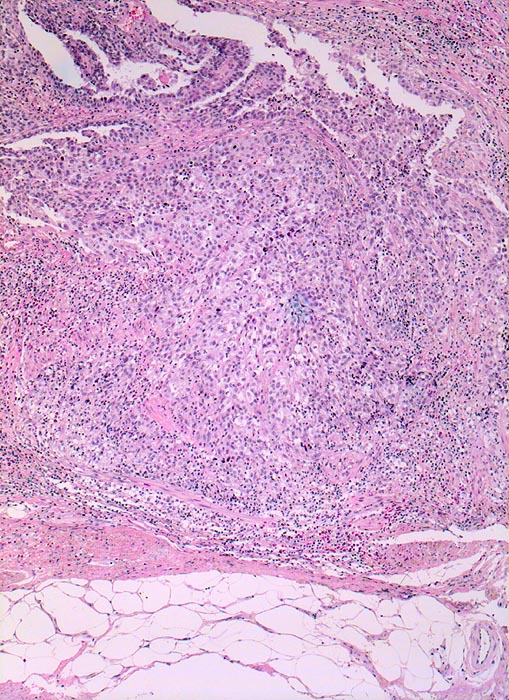

Makrohämaturie. In der Harnblasenspülflüssigkeit werden Urothelien mit schweren Kernatypien vereinbar mit Urothelkarzinom nachgewiesen. Zystoskopisch kommt in der Hinterwand ein ulzerierter Tumor zur Darstellung. Die bioptische Abklärung ergibt Anteile eines wenig differenzierten Urothelkarzinoms mit ausgedehnten Nekrosen.